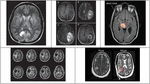

The results provided in this segment were acquired from the proposed Dual Layer Secret image sharing Approach implemented in a PC with the associated details: CPU Intel§Pentium 1.9 GHz, 64-bit operating system, Microsoft Windows 10, 4 GB of RAM, and Math Works MATLAB R2014b stage. Here, all experiments were done utilizing secret and biometric databases, while each containing 200 test images. Few of the secret medical images and the fingerprint images used for biometric fingerprint authentication scheme are given by Figures 4 and 5 respectively.

Figure 4 Secret image database.

Figure 5 Biometric fingerprint image database.